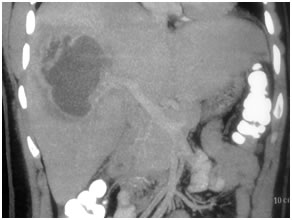

HCC in a non cirrhotic liver

Large HCC in seg 2 & 3